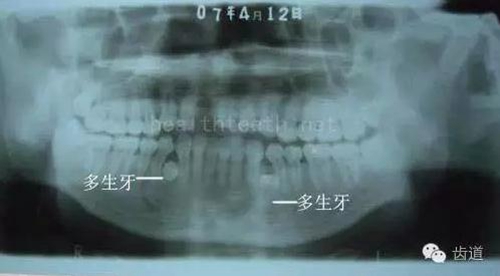

3、多生牙

病例3,同時(shí)多生兩顆牙齒

52.jpg